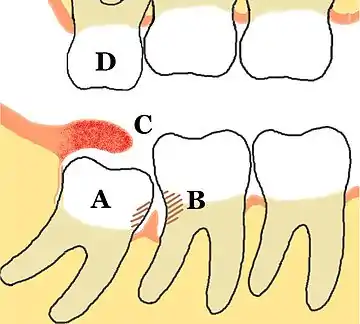

A: متراصّ نحو الأمام، ضرس عقل سفليّ ظاهر جزئيًا.

B: تسوس أسنان وخلل في دواعم الأسنان المرتبطة بالضرس الثاني والثالث، بسبب الطعام العالق، والنقص في تنظيف الفم.

C: وصاد ملتهب يغطي ضرسَ العقلٍ السفليَّ الظاهرَ جزئيًا، مع تراكم بواقي الطعام والبكتيريا تحته.

D: الضرس الثالث العلوي برز أكثر من اللازم بسبب عدم وجود تلامس مع السن المقابل، وقد يبدأ بالانطباق على الوصاد أسفلَه. الأسنان التي لا يوجد أسنان تقابلها في الفك الآخر تكون عادة حادة لأنه لم يكن هنالك أسنان تثلمها.